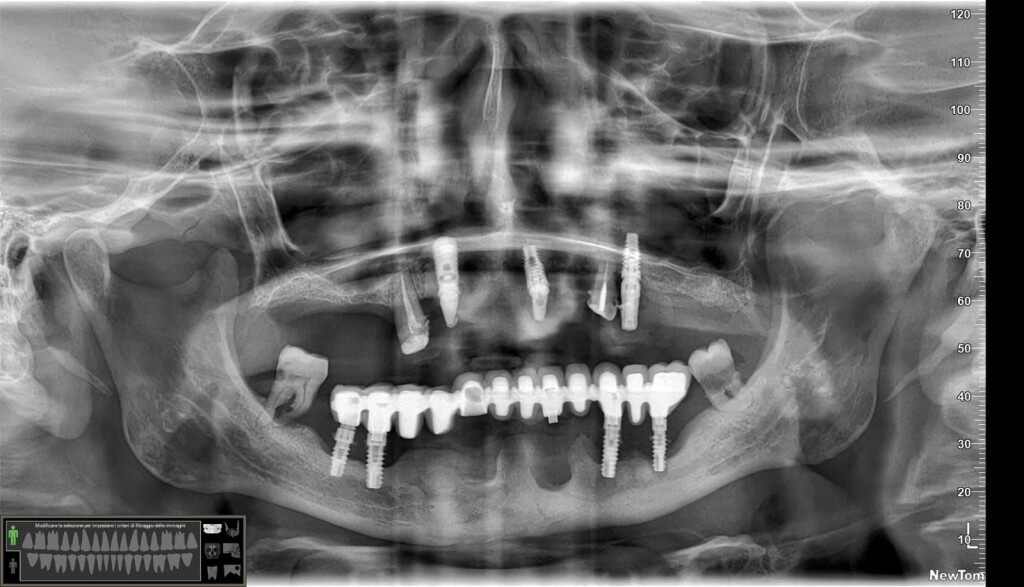

Effettivamente ci sono impianti vecchi da rimuovere e l’osso è scarso.

Nel caso di oggi vedremo il posizionamento di un impianto transinusale in questo paziente:

Ah… questa è la panoramica finale, inferiormente non ho trovato il modo per mettere 4 impianti ma solo tre… vedremo se aggiungerne uno. E non farti ingannare dall’immagine: il mentoniero di destra non è quello che sembra più distale ma quello meno visibile più mesiale.😎